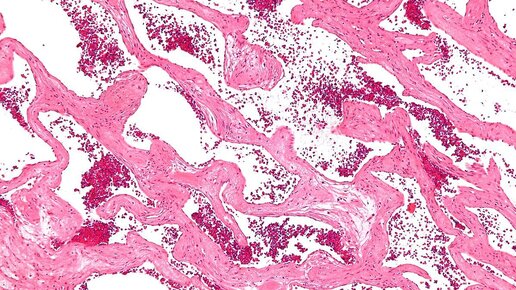

"Кавернозная гемангиома"

Слово «каверна» происходит от латинского слова «caverna» – пещера, полость. В медицине кавернами определяли патологические полости, возникающие в организме вследствие частичного некроза тканей с последующим ее распадом и отторжение омертвевшей массы. Возникает вопрос, причем тут гемангиомы? Термин «кавернозная гемангиома» появился в начале 19 века и подразумевал под собой паталогически расширенные сосуды в виде полостей различного размера и форм. Ввиду отсутствия, как-либо других уточняющих методов...